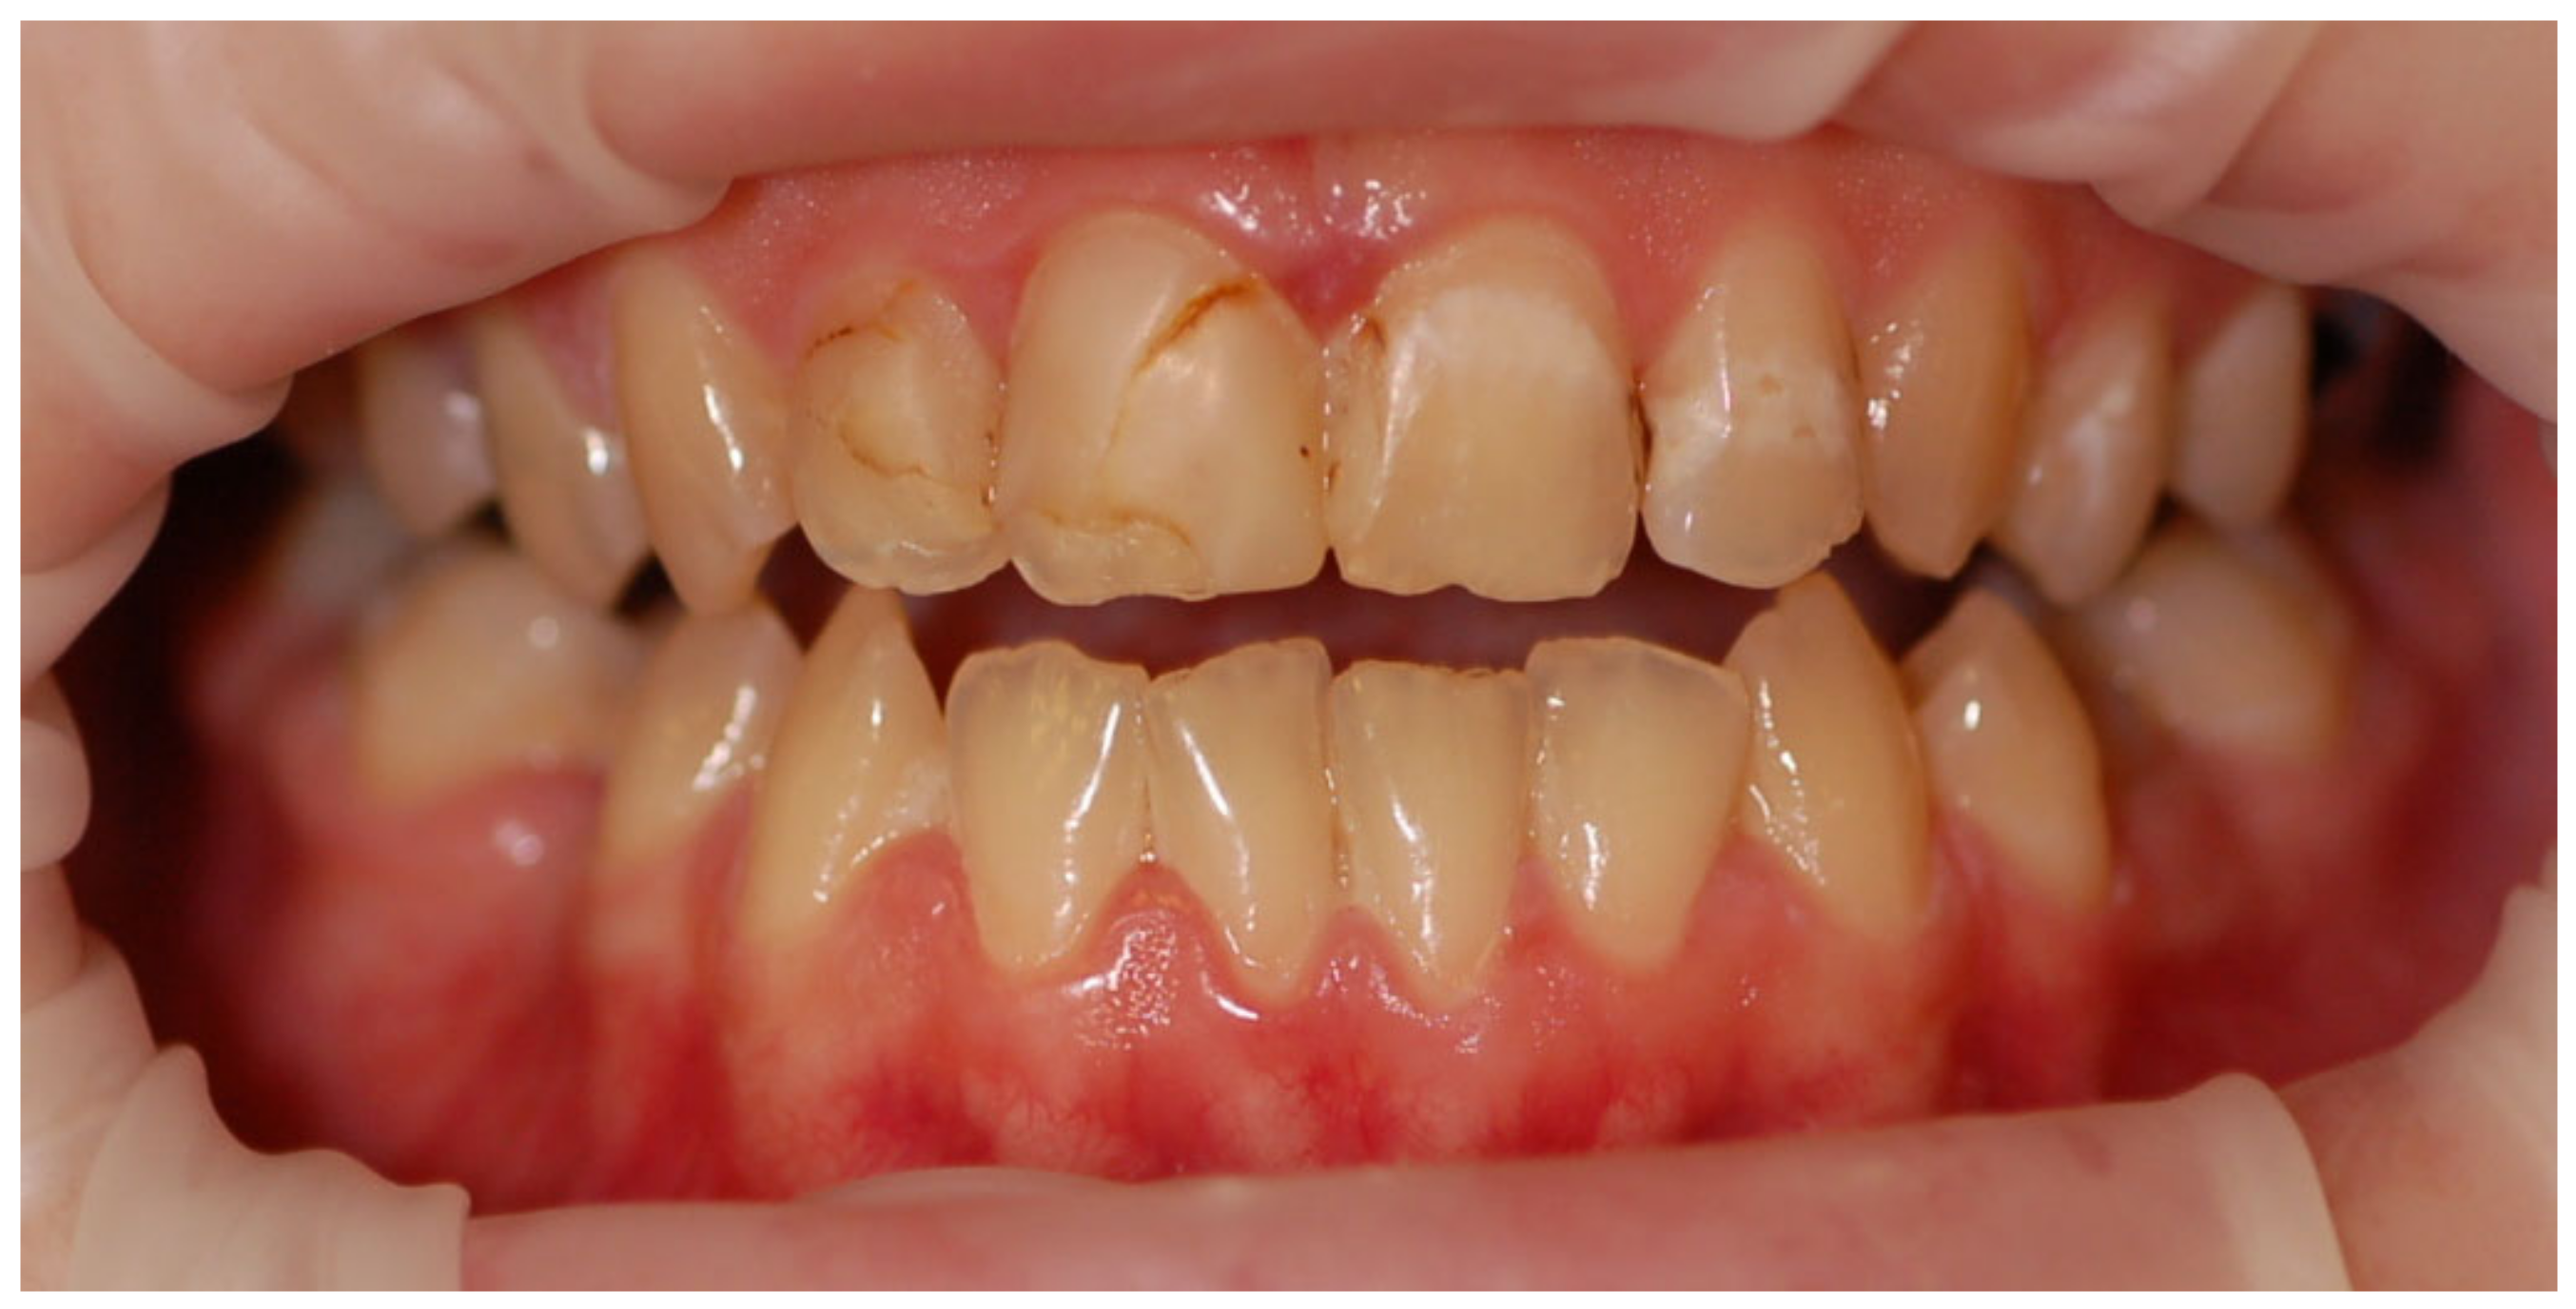

Examples of erosive defects occurring in the examined patients are presented in Figure 6, Figure 7a,b and Figure 8a–c.

Figure 8. (ac) Woman, 29 y.o. Patient with advanced erosion and tooth wear—front view and upper and lower arches.